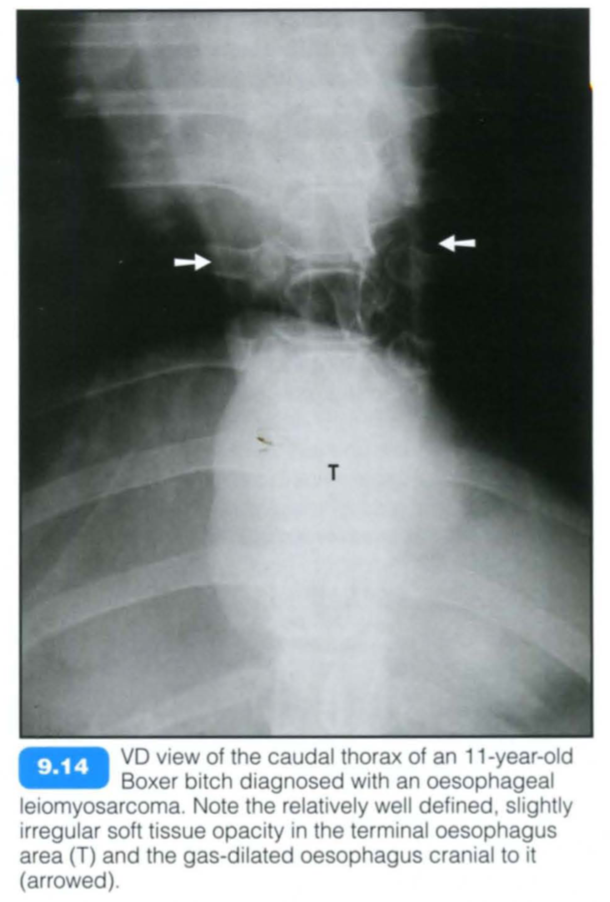

Fibrosarcoma and osteosarcoma developing from malignant transformation of Spirocerca lupi granulomas (see below) are the most common malignant oesophageal neoplasms in dogs. Other oesophageal neoplasms are extremely rare and constitute less than 0.5% of all cancers in the dog and cat. These may be of primary oesophageal, perioesophageal (lymph nodes, thyroid, thymus and heart base; see Chapter 8) or metastatic (thyroid, pulmonary and gastric carcinomas) origin.

Leiomyomas show a slow growth rate and lack of invasiveness, and on occasion may only be recognized at necropsy.

Radiographic findings include:

Contrast studies: